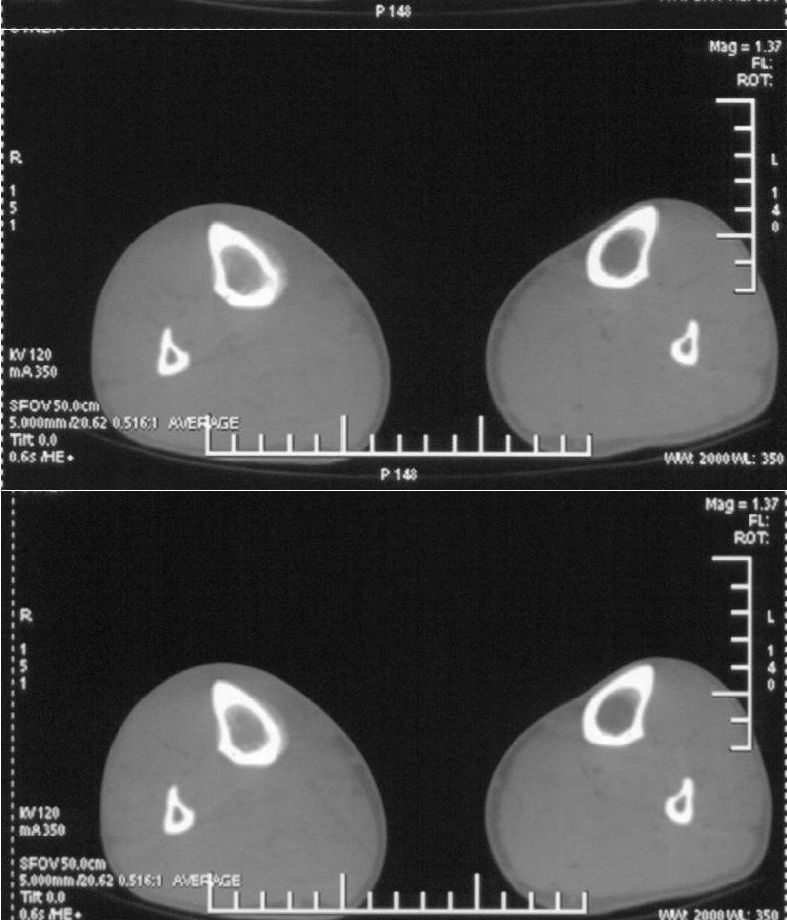

男,42岁。4个月前钢筋钝伤右侧小腿部,当时因无明显外伤,未引起重视。一周后因受伤腿部疼痛,发现肿胀,随后到当地医院进行检查(2008年4月16日)。因未发现骨质异常未引起重视,仅仅进行口服抗生素治疗处理。经过一段时间治疗但未见明显治疗效果在5月29日又进行x线检查,发现有胫骨密度上段密度增高,又进行抗炎治疗,仍未见效果。又在7月3日进行x线检查,仍然报告有胫骨上端密度增高,并建议ct检查。以下是相关检查结果:

髓腔密度呈絮状增高,胫骨上端内侧可见层状骨膜反应,考虑骨髓炎.

髓腔密度呈絮状增高,胫骨上端内侧可见层状骨膜反应,肌间隙模糊,考虑骨髓炎.

破坏、增生、骨膜反应,考虑骨髓炎